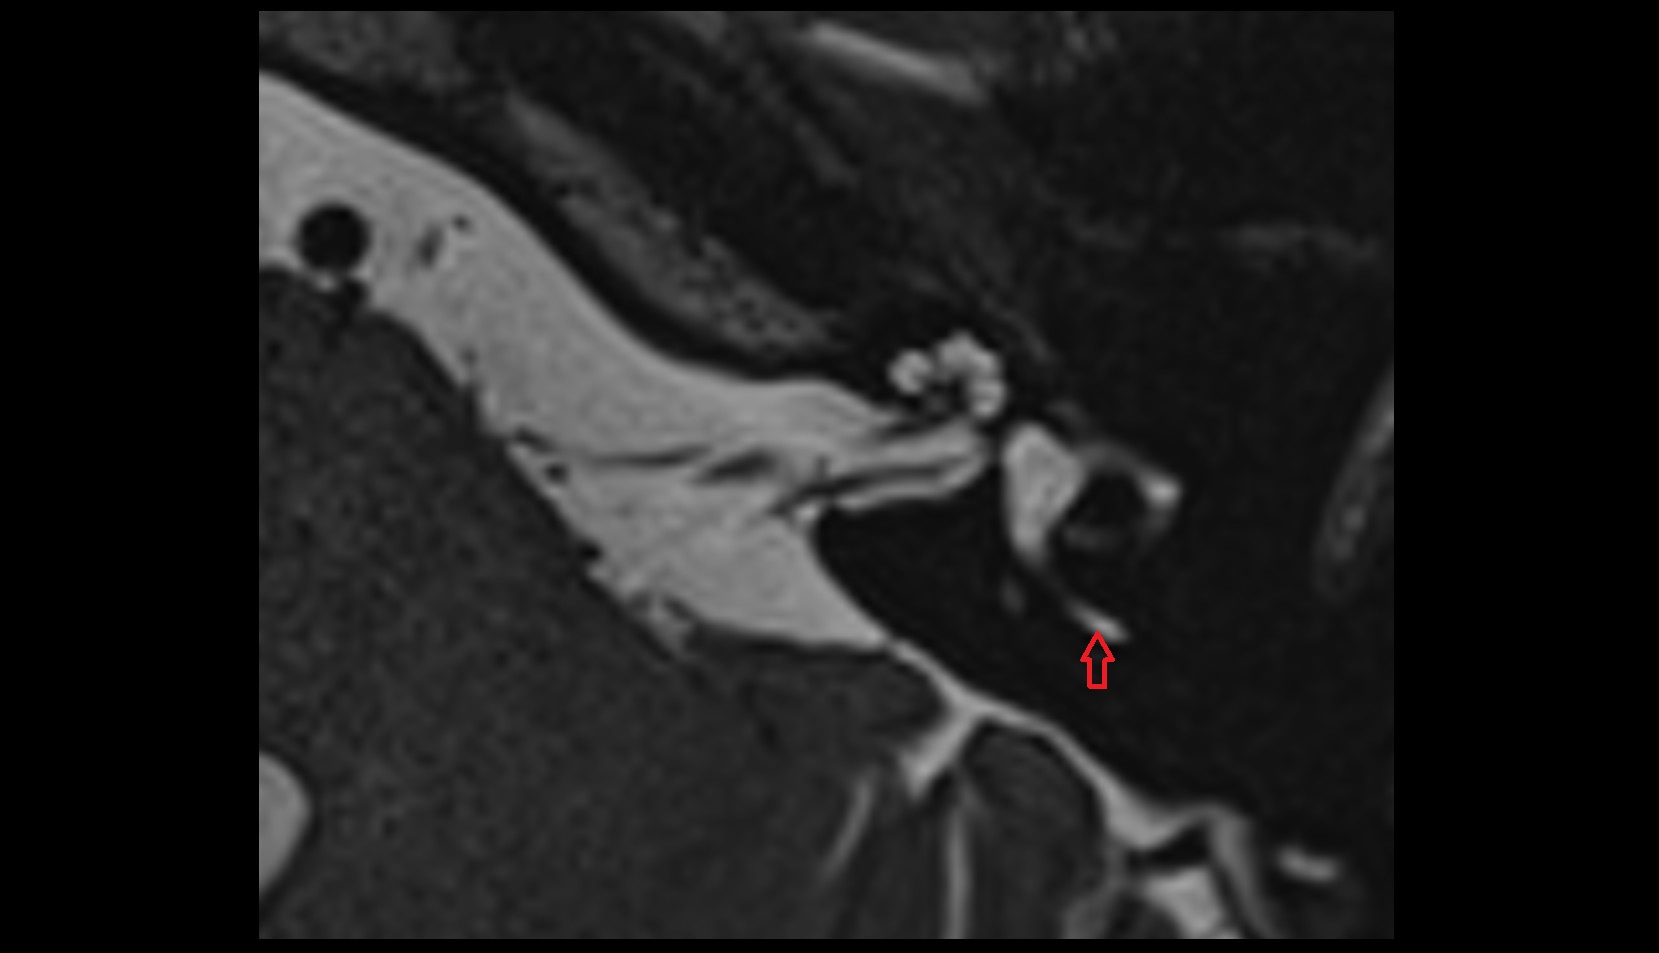

- Temporomandibular joint

- Mandibular condyle

- Mandibular fossa

- Articular disc of temporomandibular joint

- Articular eminence